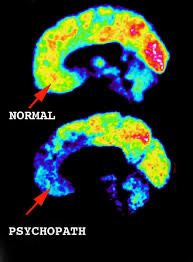

Le neuroscienze forensi hanno permesso di analizzare alterazioni cerebrali strutturali e funzionali nei soggetti con comportamenti criminali seriali. Le aree più frequentemente coinvolte sono:

1. Corteccia prefrontale: Coinvolta nei processi di controllo degli impulsi, empatia e giudizio morale. Nei serial killer, una ridotta attività nella corteccia prefrontale può tradursi in impulsività, scarsa capacità di pianificazione e assenza di rimorso.

2. Amigdala: Area chiave nella gestione delle emozioni, in particolare della paura e dell'aggressività. Uno sviluppo anomalo dell'amigdala è stato associato a ridotta risposta alla sofferenza altrui, tipica della psicopatia.

3. Sistema limbico: Responsabile dell'elaborazione emotiva e della memoria affettiva. In alcuni studi, i serial killer mostrano un iperfunzionamento limbico legato a una iper-sensibilità al rifiuto e alla frustrazione.

Per giunta, risonanze magnetiche funzionali (fMRI) hanno evidenziato schemi cerebrali atipici nella percezione del dolore e nell'attivazione dei centri della ricompensa durante la pianificazione di atti violenti.